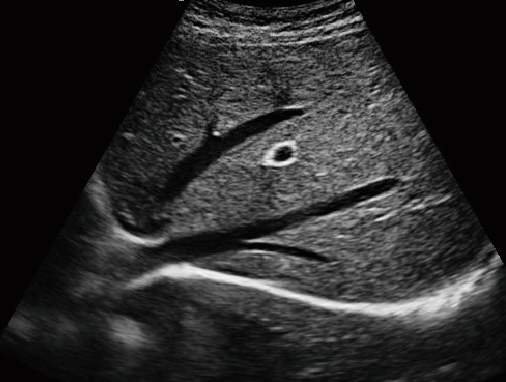

·顯示模式:B、B+B、4B、B+M、M、PW

·支持脈沖多普勒模式,可測量血流量、血流峰值、脈搏指數

·適用于各種動物的臨床腹部、胸腔,心臟、肌腱、小器官、眼球、生殖系統等的檢查